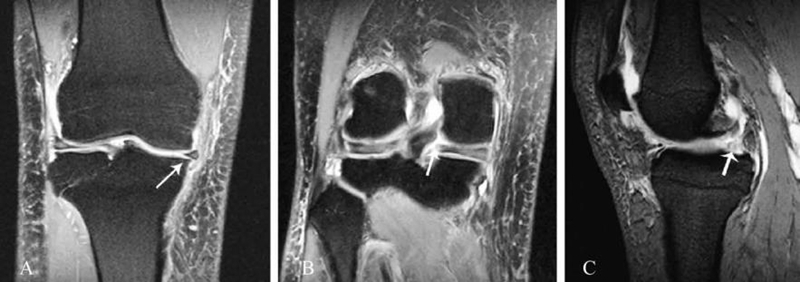

7、内侧半月板后根损伤

一般都是膝关节退行性变导致膝内翻引起,中老年女性多见。MRI上的表现有以下特征:(1)组织变性,半月板后角退行性变严重、范围广,邻近软骨可有损伤。(2)横向线性缺损,轴位上可见到内侧半月板后根处有一裂隙不连续。(3)垂直线性缺损,冠状位上可看到一裂隙出现在PCL和半月板之间,通常为高信号线状影。(4)半月板缺失,矢状位上半月板后角信号在PCL前方突然消失或被高信号填充(图7)。(5)体部外突,冠状位上内侧半月板向关节外移位>1mm为阳性,根部损伤患者半月板外移常>3mm,也称为半月板挤压征。

图7 内侧半月板后根损伤的MRI影像

A. 冠状位见内侧半月板外突;B. 冠状位内侧半月板后根垂直线性缺损;C. 矢状位内侧半月板后角缺失